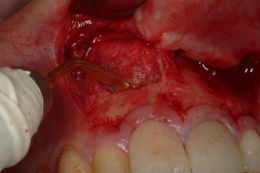

Dall'esame radiografico si evidenziano lesioni apicali a carico di tutti e due gli elementi dentari. Si sceglie per il ritrattamento ortogrado di tutti e due i denti ma per l'elemento 1.1 associato a marcato riassorbimento apicale ed apice beante si decide per una contemporanea chirurgia retrograda e chiusura in MTA.